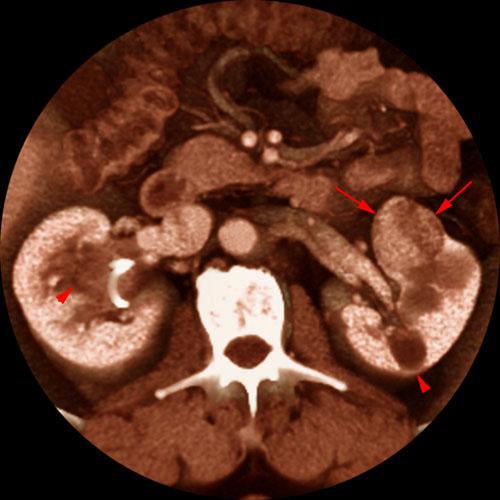

Quiste renal multitabicado e hipernefroma